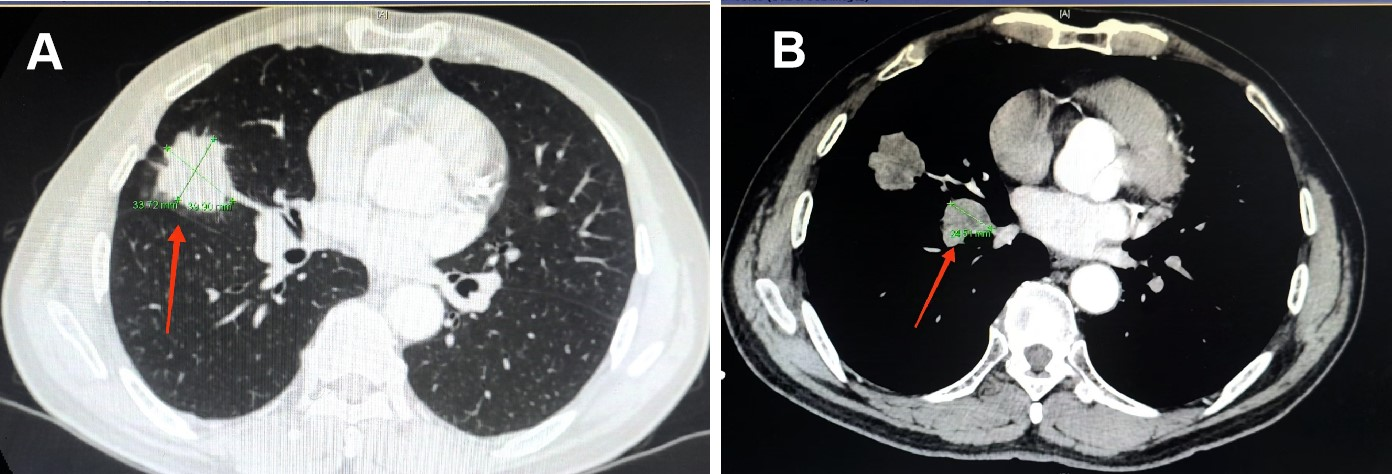

今年5月,合川72岁的向先生体检时发现右肺长了一个近4cm大小的包块(见图2),为明确诊断他慕名来到新桥医院呼吸与危重症医学中心门诊。通过入院后病理活检和系统检查,确诊为右肺小细胞肺癌T2aN2M0 IIIA期。针对向先生的病情,呼吸与危重症医学中心主任徐智教授高度重视,组织团队进行病情讨论。大家一致认为,早期(IA-IIA期)小细胞肺癌最佳治方案是手术治疗,而晚期小细胞肺癌则适宜采用化疗联合免疫治疗。对于向先生这样介于早晚期之间的IIB-IIIB病人,大多数只能按照传统方案进行化疗联合放疗,治疗后复发和转移风险较高。

图2 向先生治疗前的CT,原发肿瘤近4cm(见图A红色箭头)和肺门转移淋巴结(见图B红色箭头)